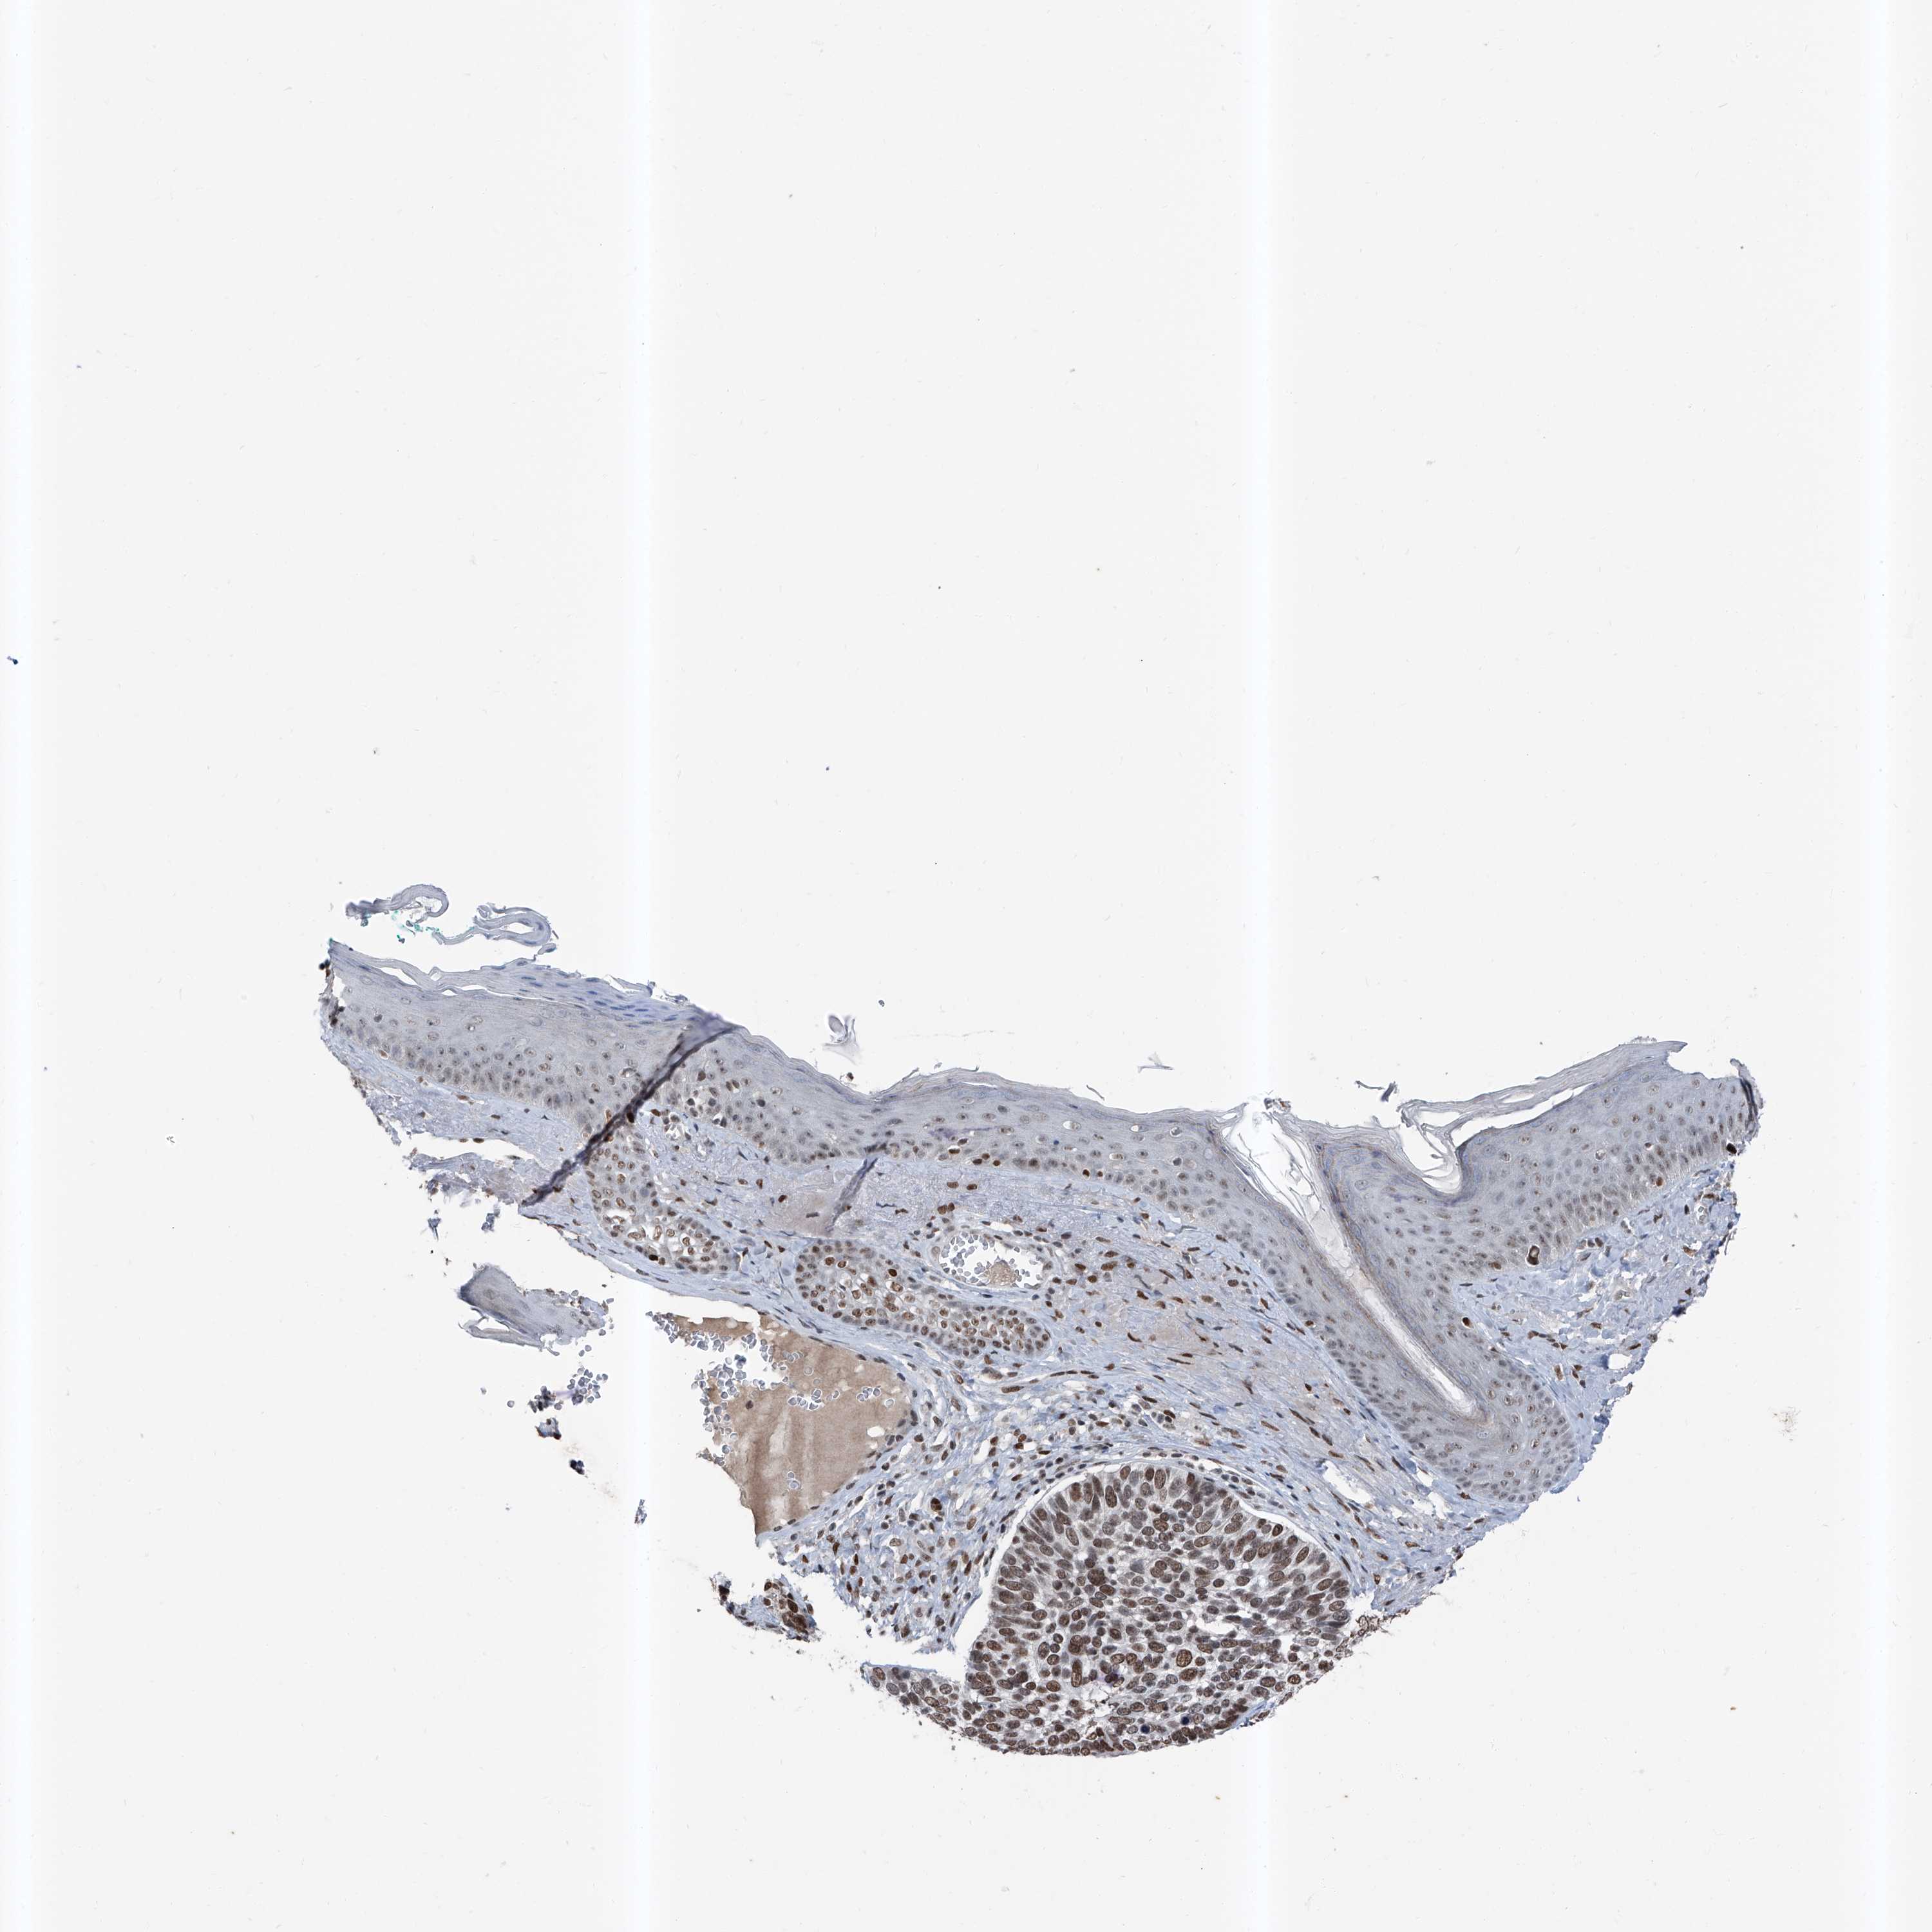

Basal cell and squamous cell cancer

SKIN CANCER - Protein expressioni

A mouse-over function shows sample information and annotation data. Click on an image to view it in a full screen mode. Samples can be filtered based on level of antibody staining by selecting one or several of the following categories: high, medium, low and not detected. The assay and annotation is described here.

Each image is clickable and will lead to virtual microscopy that enables deeper exploration of all samples and also displays staining intensity scores, fraction scores and subcellular localization as well as patient and tissue information for each sample.

Antibody HPA030472

Antibody HPA036584

Basal cell carcinoma

Squamous cell carcinoma, NOS

Squamous cell carcinoma, metastatic, NOS